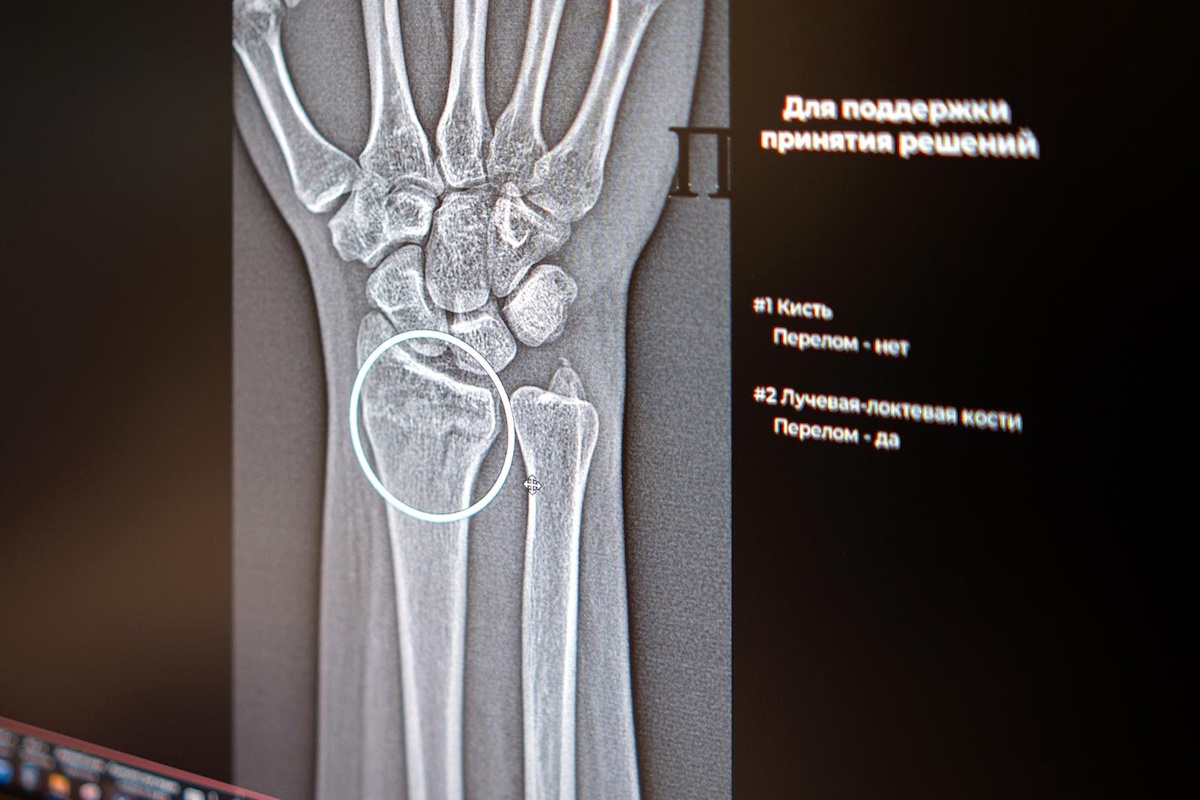

В Москве начали работу два новых сервиса на базе ИИ, предназначенных для высокоточной идентификации множественных переломов в области голеностопа и запястья. Теперь общее количество разнообразных, с точки зрения функциональности, ИИ-инструментов для специалистов в области рентгенологии достигло 60. Благодаря этому нововведению, рентгенологи смогут более оперативно и качественно оказывать медицинскую помощь пациентам, так как подобные травмы чреваты неправильным срастанием костей, деформацией суставов и ограничением их подвижности. На данный момент ИИ-технологии применяются уже в 43 различных областях клинической медицины. Цифровые технологии более пяти лет оказывают поддержку московским рентгенологам, преимущественно в процессе анализа медицинских изображений. Недавно были введены в эксплуатацию два новых ИИ-сервиса, которые помогают выявлять травматические повреждения костей в голеностопном и лучезапястном суставах – одних из наиболее функциональных и одновременно подверженных травмам

Цифровые технологии более пяти лет оказывают поддержку московским рентгенологам, преимущественно в процессе анализа медицинских изображений. Недавно были введены в эксплуатацию два новых ИИ-сервиса, которые помогают выявлять травматические повреждения костей в голеностопном и лучезапястном суставах – одних из наиболее функциональных и одновременно подверженных травмам областей. Алгоритмы автоматически выделят поврежденные зоны и произведут необходимые замеры, даже если на снимке визуализируются признаки нескольких переломов одновременно.

ИИ-технологии в области лучевой диагностики анализируют изображения, опираясь на множество параметров, помогают в проведении требуемых расчетов и ускоряют процесс описания снимков. Они способны обнаруживать даже незначительные трещины и указывать врачу на наличие множественных переломов в одной и той же области. Точная диагностика напрямую влияет на выбор оптимальной стратегии лечения, сообщили в столичном департаменте здравоохранения.